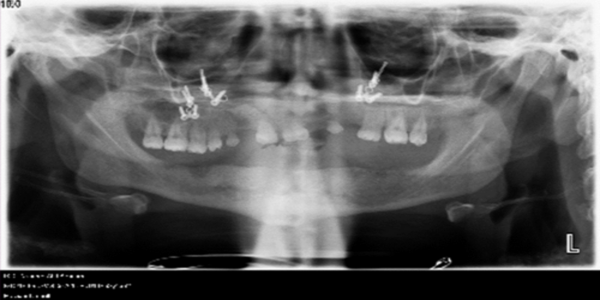

Computer-Aided Implant Planning: Utilizing AI for Precise Placement and Predictable Outcomes